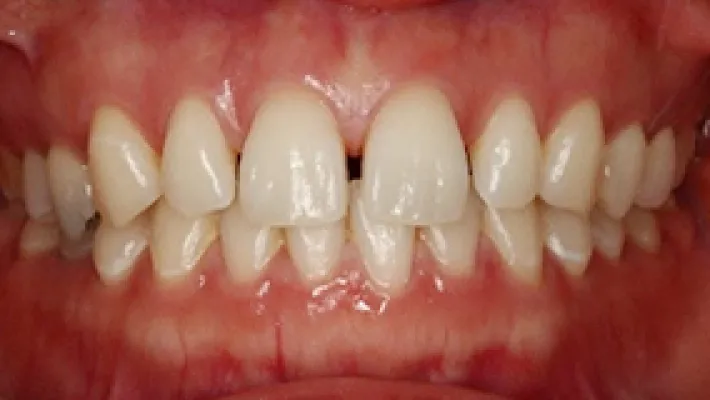

上前歯8本 ラミネートベニア

施術前

施術後

削らないラミネートベニアで歯の大きさ・すきっ歯・乳歯・矮小歯を改善した症例です。

歯肉整形と削らないラミネートベニアを行い、曲がっていた歯列が左右対称に見えるように改善しました。

*ラミネートベニアはすきっ歯を埋めることはできますが、出っ歯や歯の出っ張りを引っ込めることはできません。出っ歯や出っ張り部分の歯を削れば、歯の形を修正することもできます。